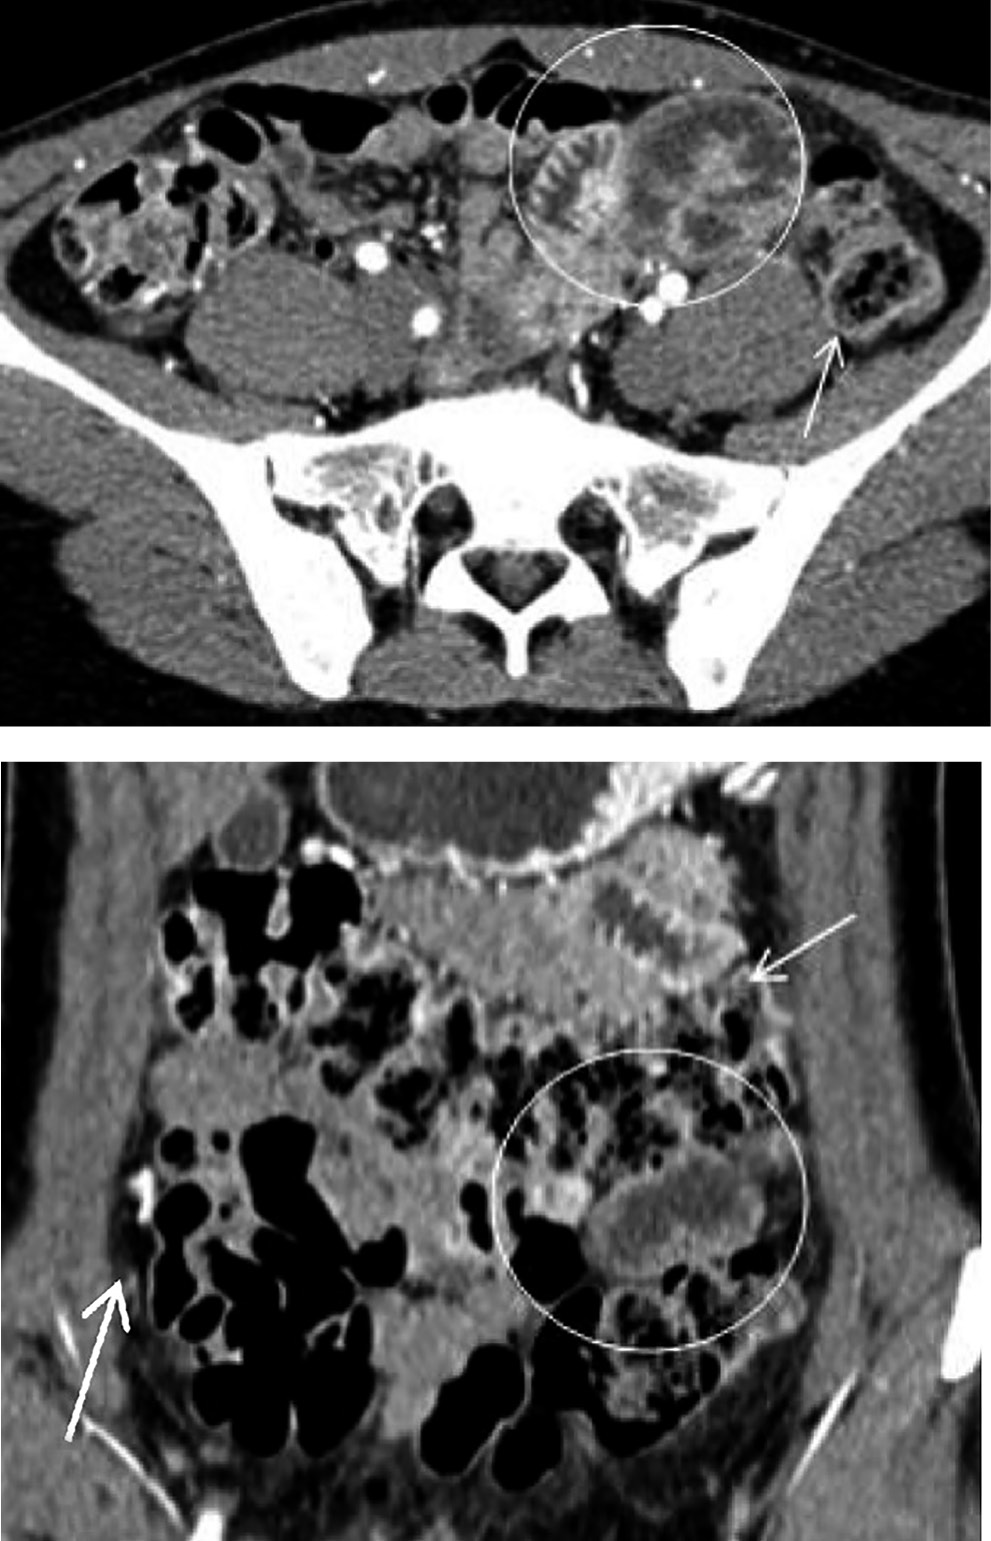

Больная Л. предъявляла жалобы на чувство переполнения в эпигастральной области после приема пищи, возникающее несколько раз в неделю. При КТ-обследовании выявлена дислокация умеренно расширенных петель начального отдела тощей кишки в левую парадуоденальную ямку (рис. 3). Аналогичные данные КТ-исследования и клиническую картину болевого синдрома мы наблюдали у больного П.

Рис. 3. Пациентка Л., 63 года. Врожденная левосторонняя парадуоденальная грыжа

Примечание. Артериальная фаза (а, б) и венозная фаза контрастного усиления (в). На изображениях (а, б) определяются расширенные петли тонкого кишечника (овалы). Восходящая левая брыжеечная артерия и нижняя брыжеечная вена (стрелка) располагаются кзади от грыжевого мешка и ограничивают его с медиальной стороны. На более краниальных сканах обозначенные сосуды пересекают верхний край грыжевых ворот и располагаются спереди от грыжевого мешка (не представлены). На изображении (в) отчетливо видны входящая в грыжевые ворота 4-я часть двенадцатиперстной кишки (пунктирная стрелка) и выходящая петля тощей кишки (стрелка), а также натянутые сосуды брыжейки (изогнутая стрелка).

Рис. 4. Пациентка В., 58 лет. Процесс формирования внутренней грыжи: исследование выполнено вне периода обострения

Примечание. Смещение большей части двенадцатиперстной кишки (стрелка) и начальной петли тощей кишки (обведена овалом) в направлении верхней брыжеечной артерии (пунктирная стрелка). Смещенная петля тощей кишки умеренно расширена (диаметр 30-32 мм) и располагается над брыжейкой поперечной ободочной кишки. На изображении (в) по краю расширенной петли видны расширенные сосуды брыжейки (изогнутая стрелка).